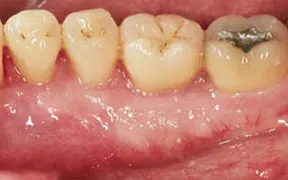

This patient is missing a lot of gum tissue around the neck of the tooth with the white arrow.

The yellow arrows are pointing to the line of healthy attached tissue, You can see how much space there is between the yellow arrows and the neck of the tooth.

This is the result of a gingival graft, which shows the presence of pink and healthy attached gingival tissue around the neck of the tooth. The prognosis for this tooth is excellent and the procedure took one appointment.